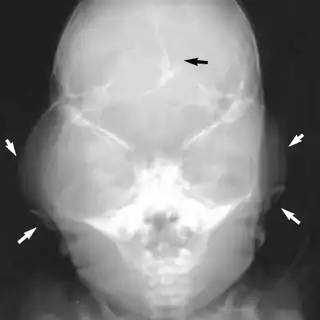

Beare–Stevenson cutis gyrata syndrome is a rare genetic disorder characterized by craniosynostosis (premature fusion of certain bones of the skull, sometimes resulting in a characteristic 'cloverleaf skull'; further growth of the skull is prevented, and therefore the shape of the head and face is abnormal) and a specific skin abnormality, called cutis gyrata, characterized by a furrowed and wrinkled appearance (particularly in the face and on the palms and soles of the feet); thick, dark, velvety areas of skin (acanthosis nigricans) are sometimes found on the hands and feet and in the groin.[2][3]